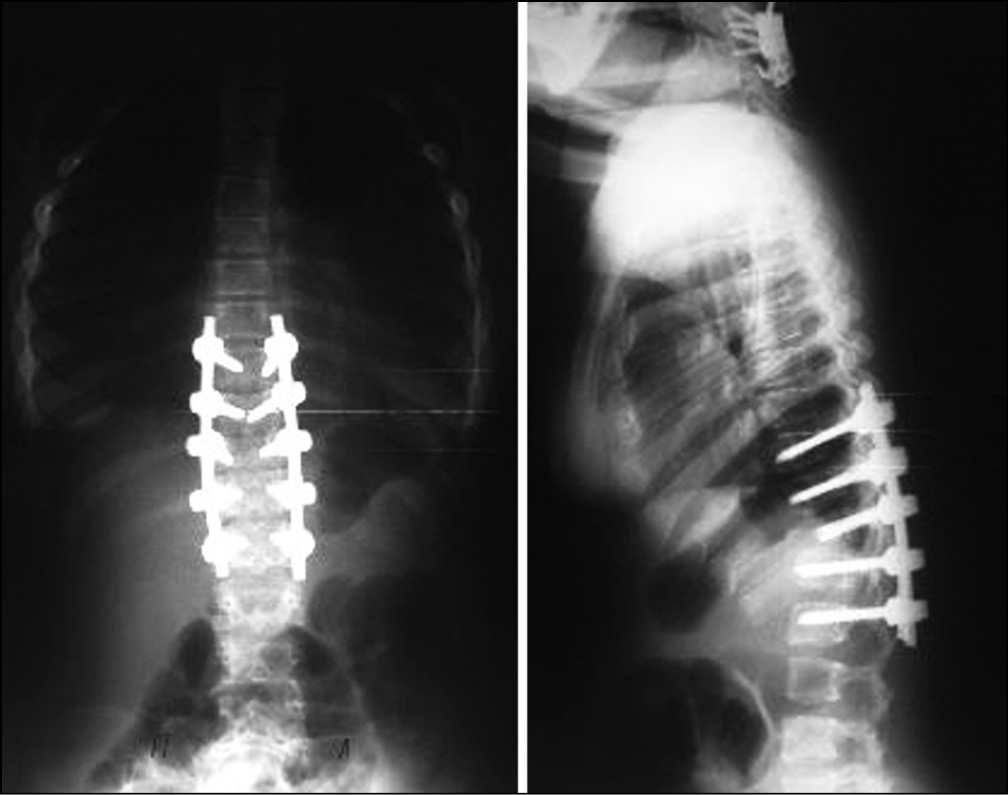

В связи с вышеуказанными изменениями пациентке выполнена операция: транспедикулярная фиксация Th9–L1, коррекция кифотической деформации. Ламинэктомия позвонка Th11, декомпрессия спинного мозга. Задний спондилодез аутокостью, угол коррекции составил 30° (рис. 5). В послеоперационном периоде отмечено снижение болевого синдрома до 3 баллов по визуально аналоговой шкале. Назначено ношение грудопоясничного корсета на 3 мес. Через полгода на контрольном осмотре пациентка ходит самостоятельно без поддержки. На контрольных рентгенограммах через 4 года потери коррекции не выявлено.

Рис. 5. Рентгенограммы грудопоясничного отдела позвоночника после операции, отмечается выраженная коррекция деформации, угол коррекции составил порядка 30º